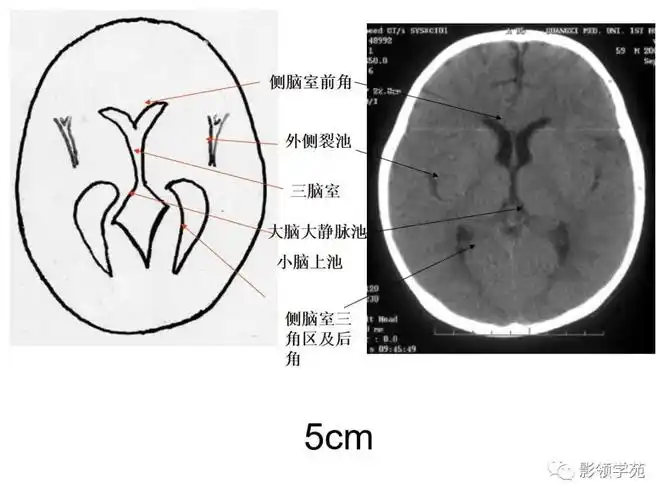

基底节区层面颅脑ct断层解剖

【解剖入门】颅脑ct断层(中英文对照)